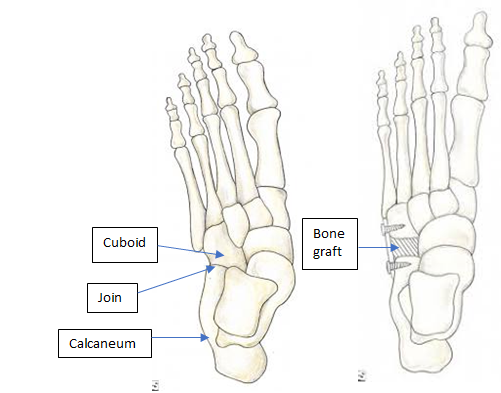

The heel bone is cut and a bone graft taken and reinserted to lengthen the lateral border of the foot, increasing the arch height and stabilising the foot. It does not fuse any joints and the major movements of the foot are preserved, although the direction of movement is changed to prevent excessive rolling in of the foot.

Calcaneocuboid distraction arthrodesis

In adults, lengthening the lateral border of the foot remains very effective in correcting a flat foot. However, the traditional Evans procedure is not always well tolerated with arthritis sometimes developing in the adjacent calcaneocuboid joint. This approach lengthens the lateral border of the foot by fusing the calcaneocuboid joint using a bone graft, preventing arthritis from occurring in this joint.

The downside is a stiffer foot and some patients still complain of pain affecting the lateral border of the foot. The fusion site can also be painful if the bones do not unite with the risk being around 2-4%.